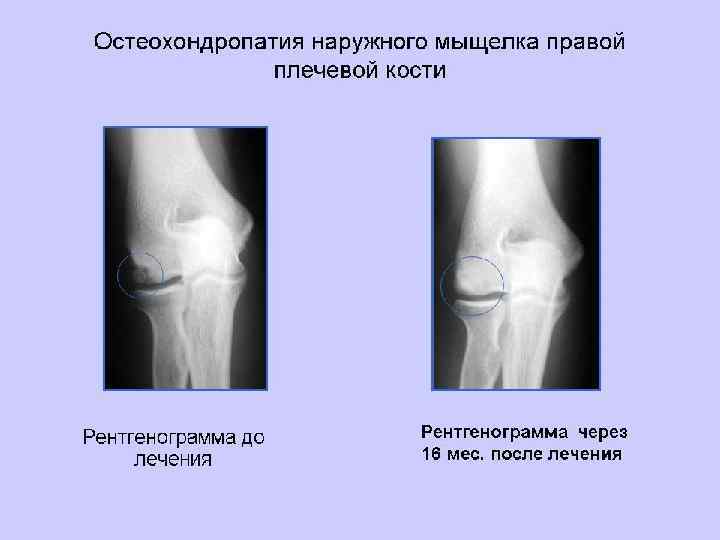

Диссецирующая остеохондропатия локтевого сустава у 25 летнего мужчины. Жалобы на боли в локтевом суставе, временами явления ущемления. На прямой рентгенограмме между головкой лучевой кости и головчатым выступом плеча видно небольшое свободное тело в форме чечевицы. Более крупное округлое тело „загнано" или в локтевидную ямку плеча (fossa olecrani humeri), или же в венечную ямку (fossa coronoidea humeri) прямая рентгенограмма не устанавливает точной локализации.